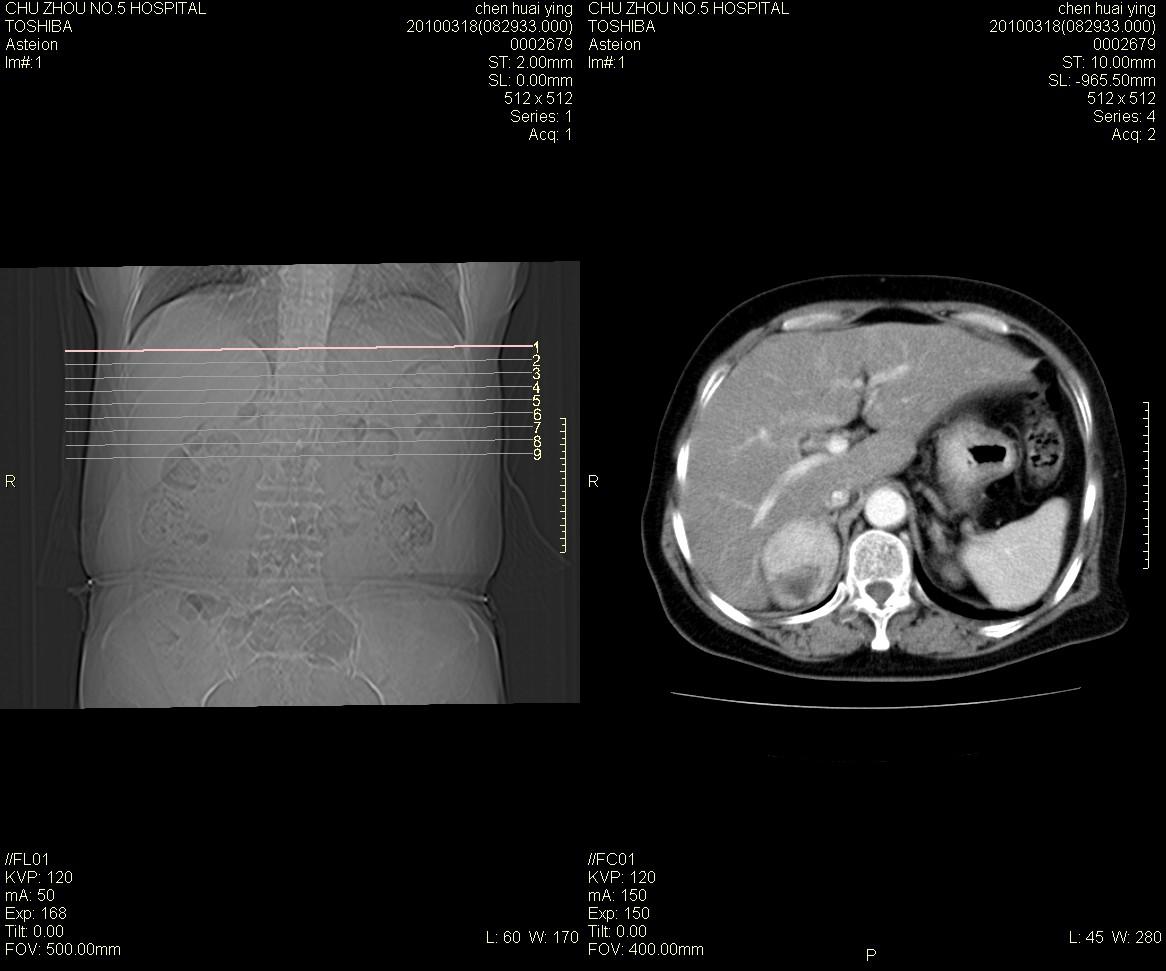

标题: CT25148 肾上腺增强

ct25148增强图片

动脉期太早了,扫的有点低。考虑良性占位右侧肾上腺嗜铬细胞瘤并坏死囊变可能性大,神经鞘瘤不排除。

右侧肾上腺占位性病变,病人是否有高血压?嗜铬细胞瘤?

右侧肾上腺嗜铬细胞瘤并坏死囊变可能性大

考虑双侧肾上腺肿瘤性病变。